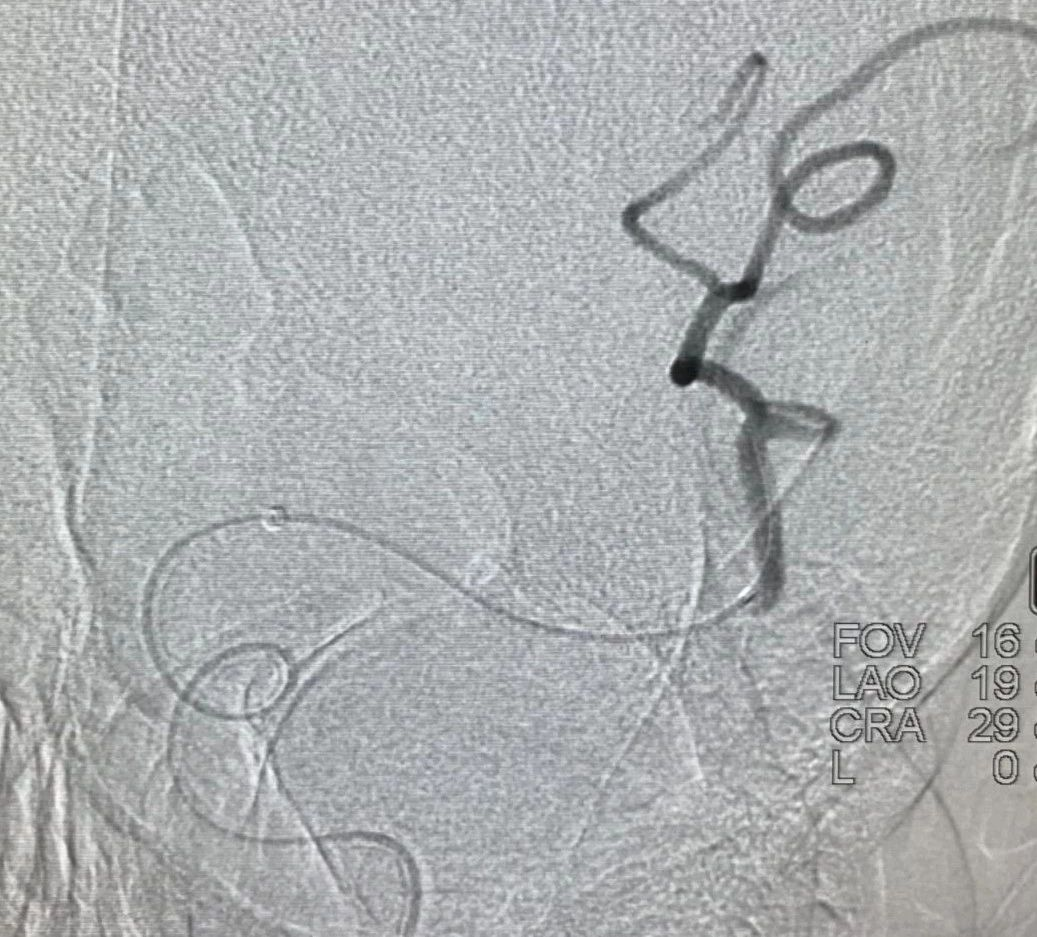

一、该患者血栓负荷较重,得益于加奇申翼®取栓器独特的前段“网兜”设计,经历2次取栓,但无明显血栓逃逸。此外,该产品还具有较长的工作长度和更大的网孔设计,良好的血栓嵌合能力以及优秀的抗折性和贴壁性,支架可以整体显影,并可以在内腔为0.017 inch的微导管输送。

二、对于支架与血栓嵌合处可能出现支架打开欠佳,通过推挤、按摩支架可使支架打开良好,增加对血栓的切割力,提高取栓成功率。